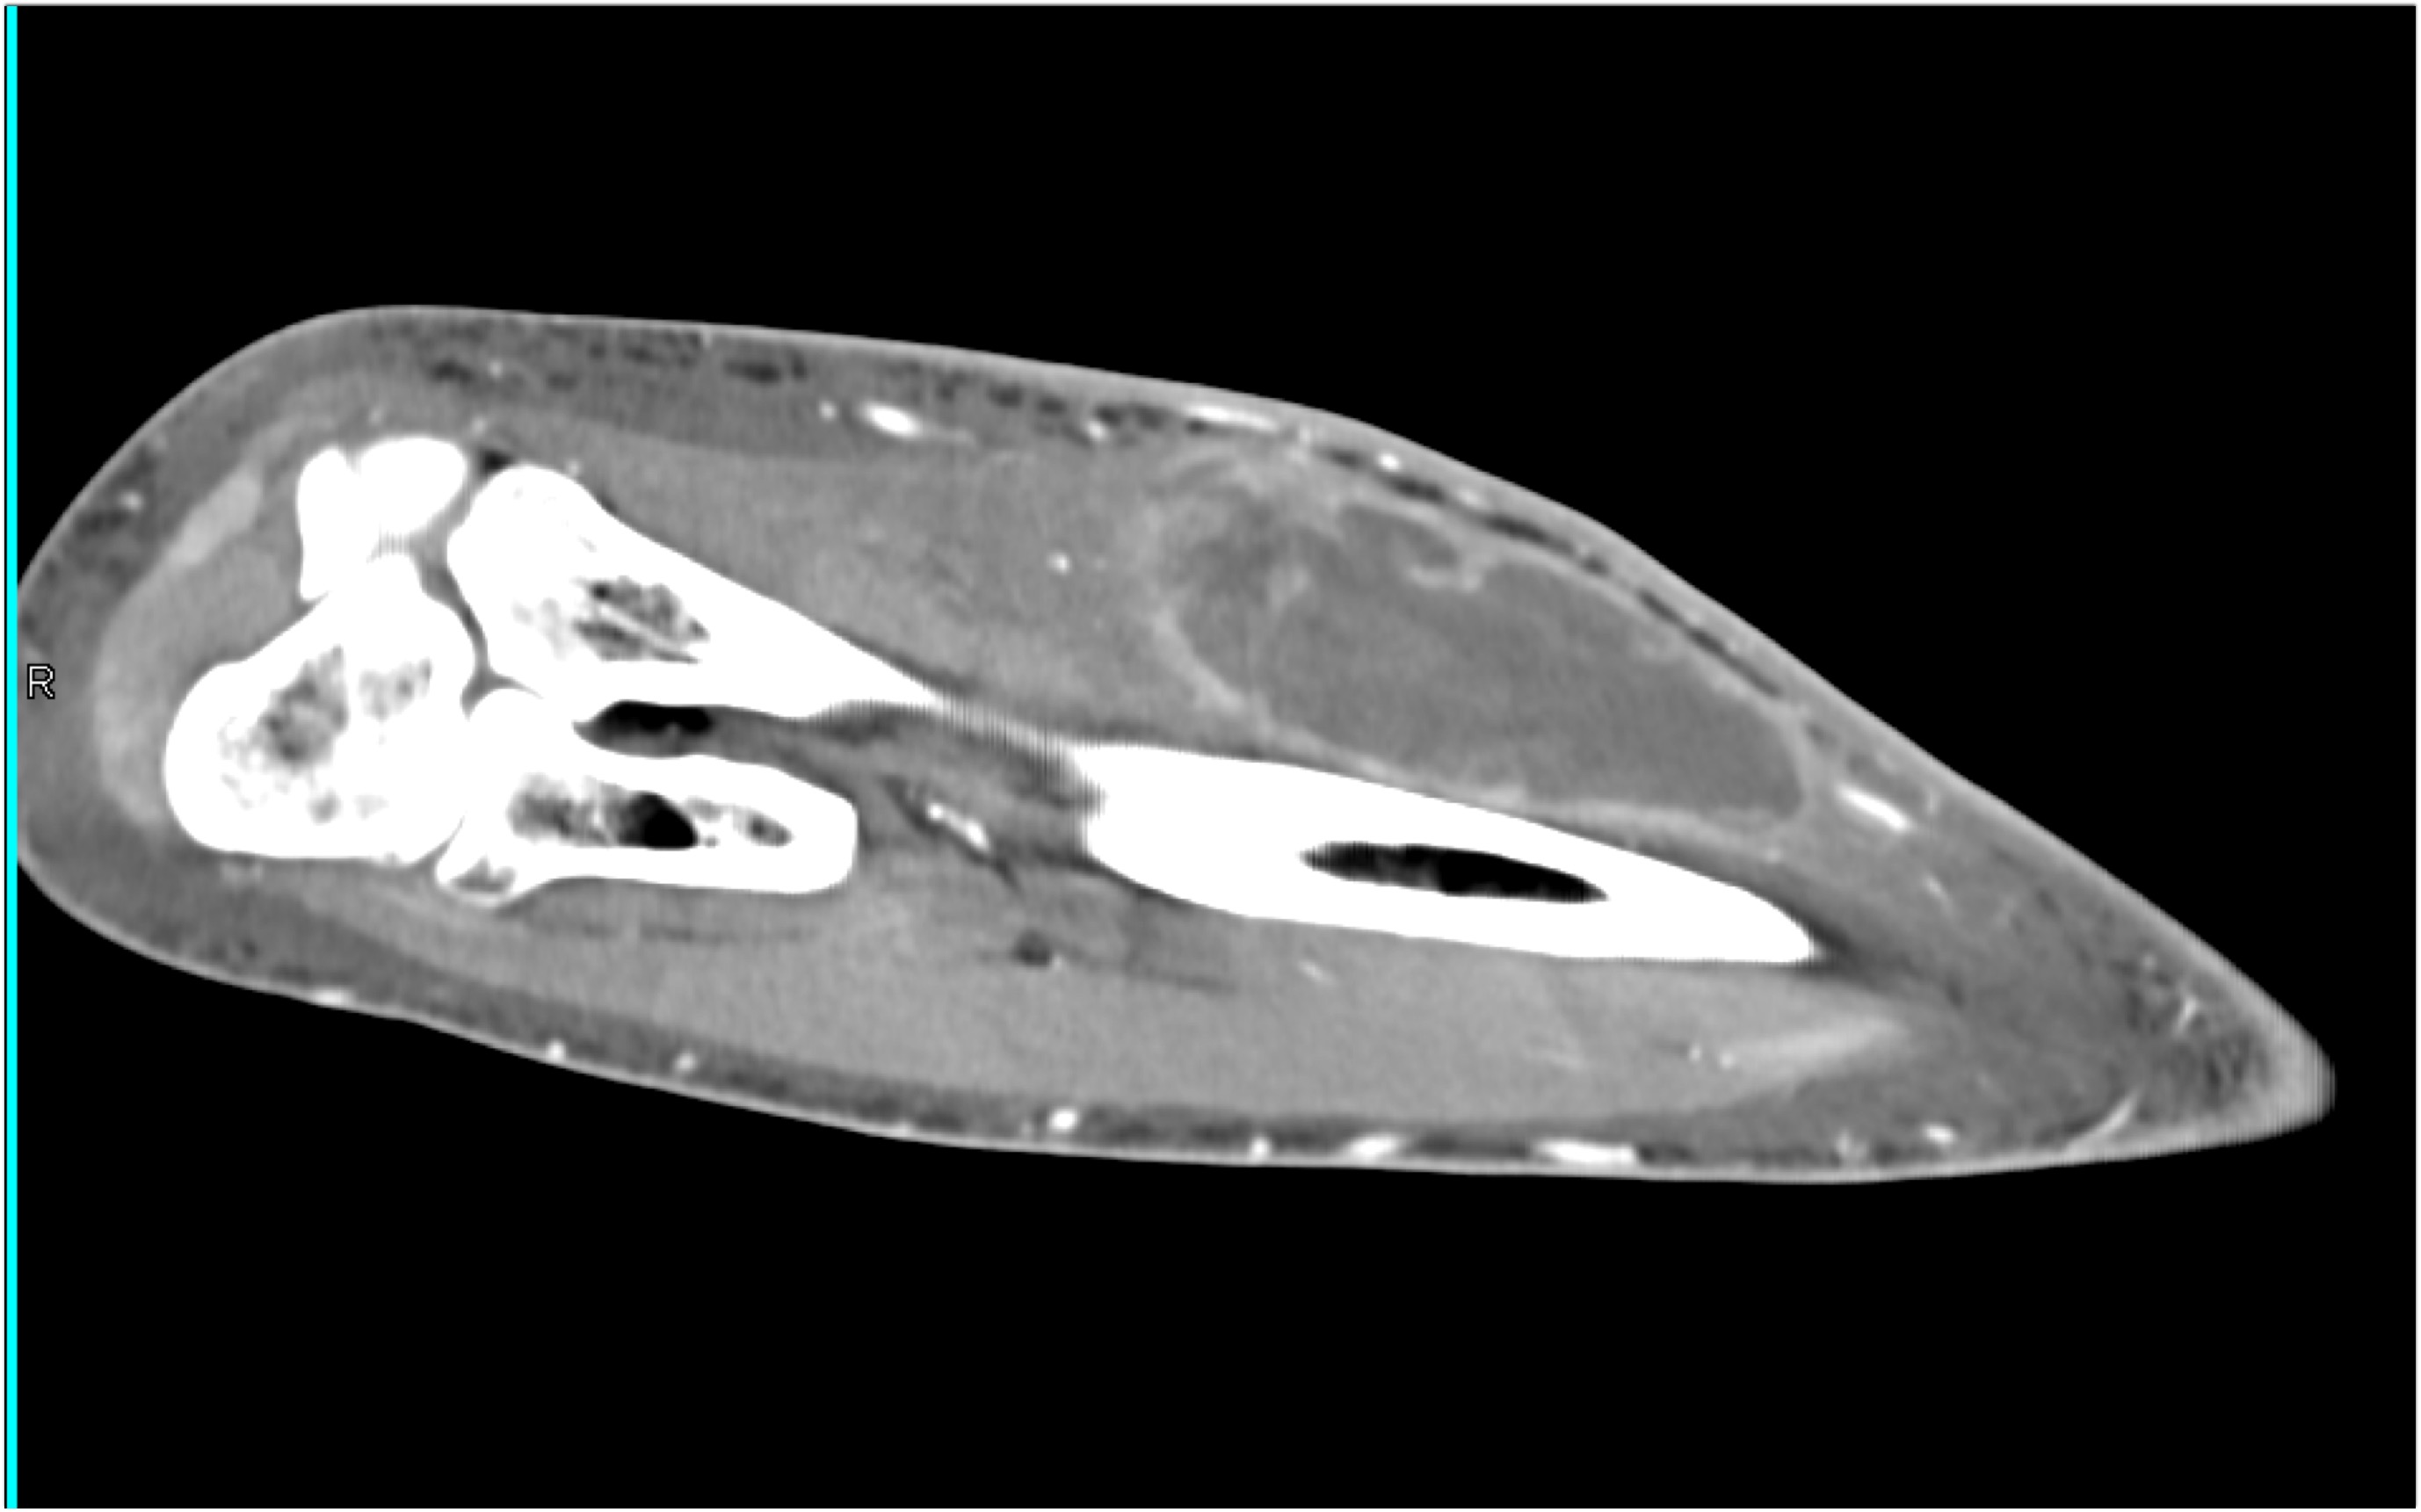

2) In this patient on dialysis for ESRD the best diagnosis is?

normal bypass graft

AV fistulae with aneurysms

vasculitis

infectious vascular disease